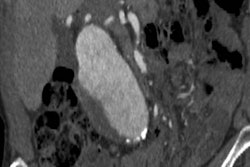

The U.S. Preventive Services Task Force (USPSTF) has reaffirmed with no major changes its 2014 recommendations on using ultrasound to screen for asymptomatic abdominal aortic aneurysm (AAA), in a new statement published online December 10 in the Journal of the American Medical Association.

After consideration of public comments on its draft recommendation statement, the USPSTF has finalized its guidance on AAA screening, which reaffirms the task force's 2014 recommendations with no substantial changes. The 2019 guidance for ultrasound AAA screening includes the following recommendations: